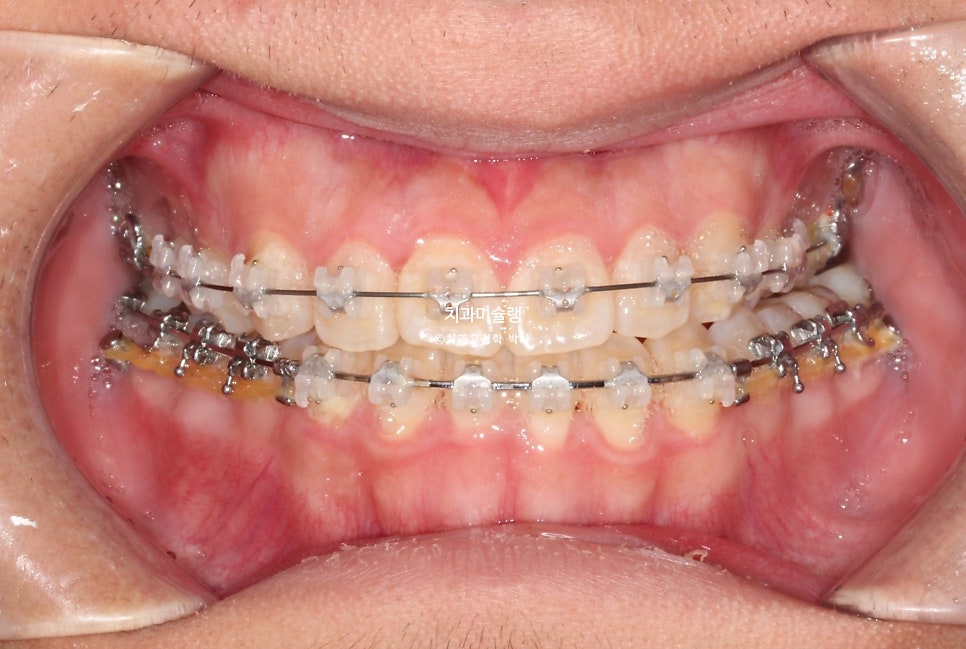

아래 치열에만 클리피씨 장치를 부착하고 약 6개월간 아래치열을 먼저 진행 한후 위 치열에도 뒤늦게 클리피씨 장치를 붙입니다.

아래가 위보다 치아이동량이 많고 오래걸리는 경우라서 위 치열 장치 부착 시기를 늦추면, 환자분의 불편감도 그만큼 줄어듭니다.